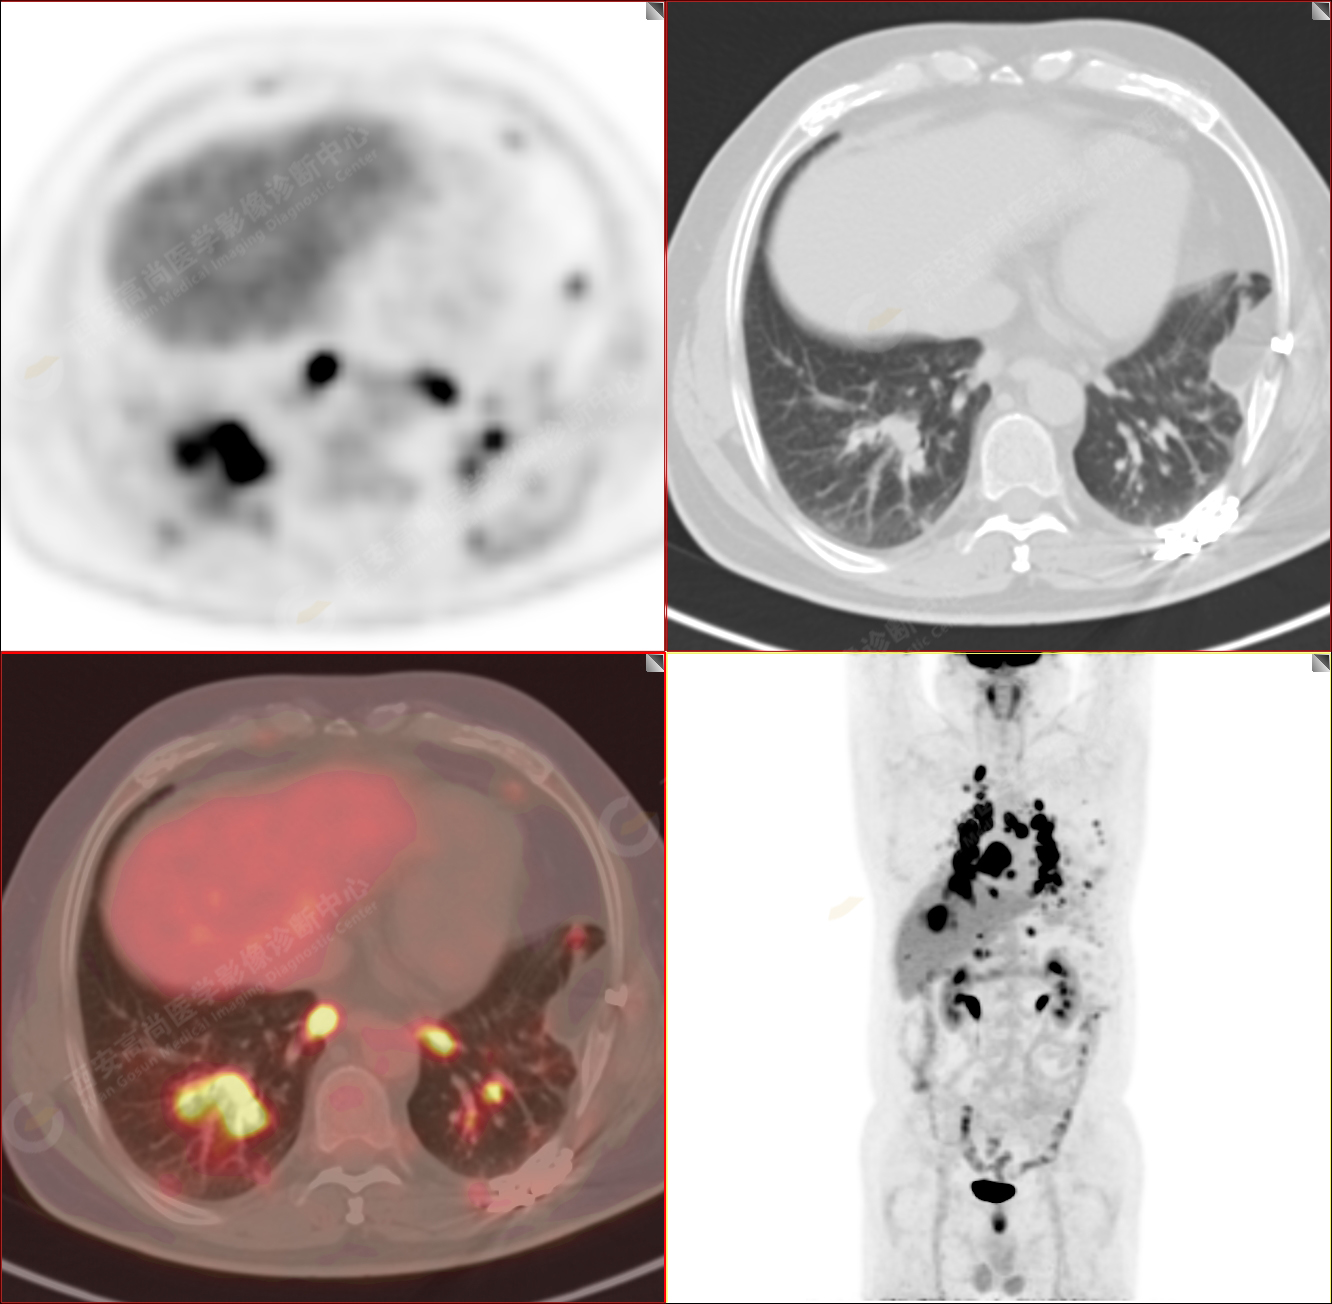

PET/CT-MR診斷結(jié)節(jié)病雙肺及全身多發(fā)淋巴結(jié)廣泛累及1例【西安高尚病例】

男性,53歲,頭暈半月入院,CT發(fā)現(xiàn)肺內(nèi)腫塊,雙肺多發(fā)大小不等實(shí)性及粟粒樣結(jié)節(jié),雙肺門(mén)及縱隔多發(fā)腫大淋巴結(jié)。病程中無(wú)發(fā)熱、胸悶氣及胸部不適。既往:左側(cè)肋骨外傷史。

PET-MR圖像